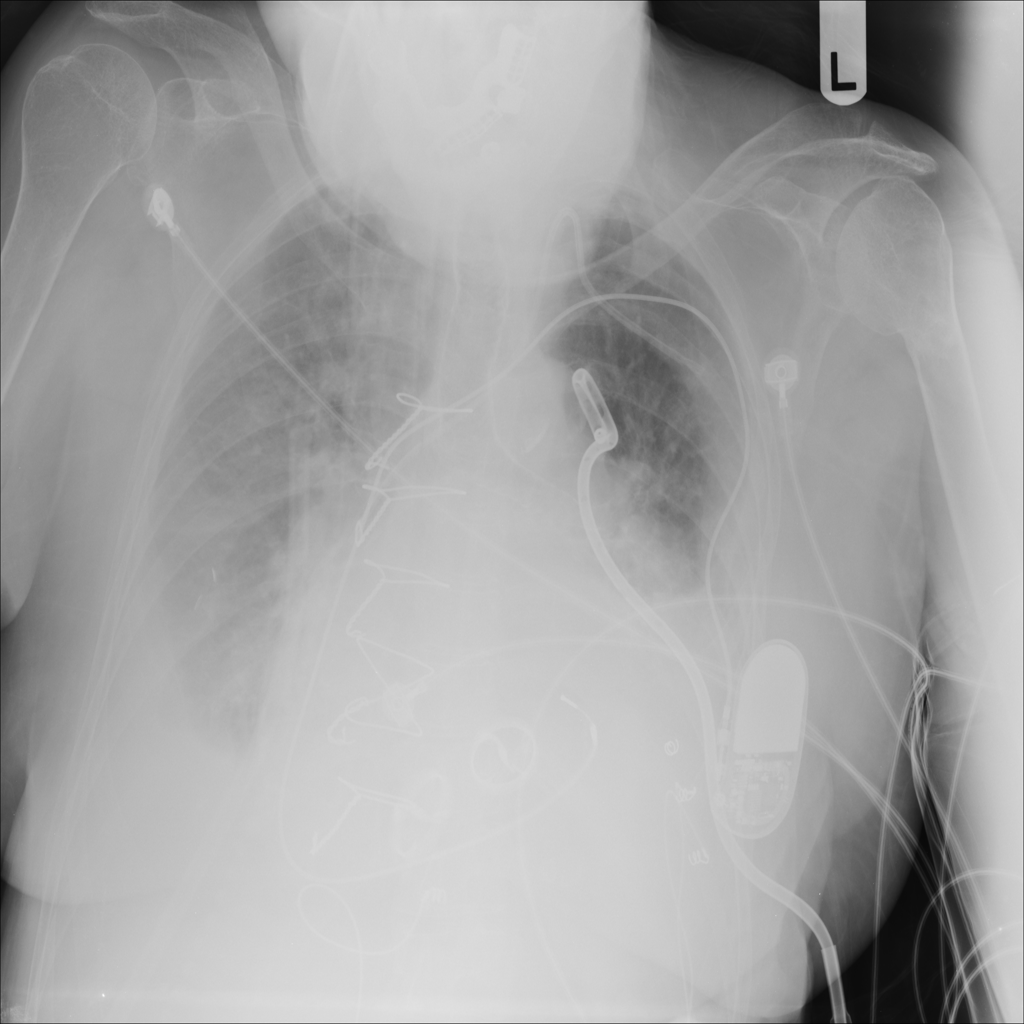

Pleural Effusion

Pleural effusion means extra fluid has collected around the lung in the pleural space. It can happen with heart problems, infection, inflammation, or other underlying conditions.

Showing up to 90 reference images for Effusion.

PAT-C0E5 · IMG-002Effusion

PAT-C0E5 · IMG-002

PA